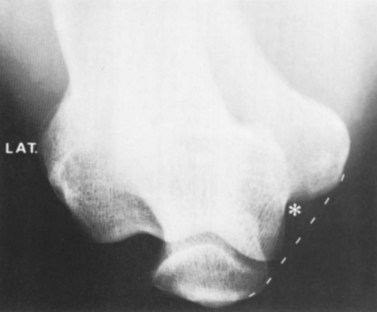

In cases of MOT, calcification is slow, with fibroblasts beginning to differentiate into osteoblasts about 1 week after injury. Radiographic evidence of bone formation is usually visible after 3 weeks (Fig. 8.4). By 6–7 weeks after injury, the calcified mass generally stops growing. Total reabsorption may occur with minor lesions, but more major conditions may continue to show remnants of the mass. The mass rarely interferes with muscle contraction, so excision is not normally required (Estwanik and McAlister, 1990).

image

Figure 8.4 X-ray showing myositis ossificans traumatica (MOT).

From Magee (2002) with permission.